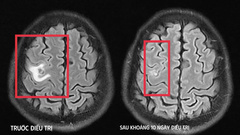

9 ngày sau, tình trạng nuốt vướng tăng lên, nuốt nghẹn và đau tức ngực nhiều, không ăn uống được. Đến khám tại Bệnh viện 19-8, bệnh nhân được chỉ định nội soi thực quản - dạ dày. Khi nội soi bác sĩ thấy dị vật đâm sâu vào thành thực quản nghi thủng và rò khí quản, nên đã chỉ định chụp CT lồng ngực. Kết quả chụp dị vật cản quang kích thước 2x3 cm, đâm xuyên qua thành thực quản, khí quản và thực quản thâm nhiễm xung quanh.

Vietnamnet dẫn lời Bác sĩ - Thiếu tá Phạm Thị Việt Anh, Phó trưởng Khoa Nội tiêu hoá (Bệnh viện 19-8) cho biết, may mắn dị vật chưa bị rò sang khí quản và người bệnh được gắp dị vật an toàn qua nội soi. Sau gắp được 1 mảnh xương lớn, phức tạp, tại chỗ cắm của đầu xương vết loét rỉ máu và chảy mủ.